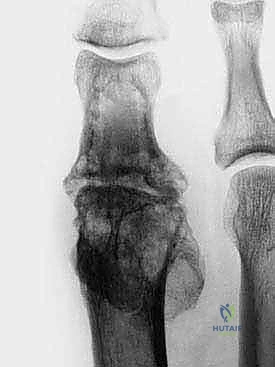

2. النخر اللاوعائي (Avascular Necrosis - AVN)

حالة يموت فيها جزء من رأس العظم المشطي بسبب انقطاع التروية الدموية عنه. قد يحدث هذا بعد صدمة شديدة، أو كمضاعفات لجراحة سابقة، أو لأسباب مجهولة. يؤدي موت العظم إلى انهياره وتفتته، مما يترك فجوة كبيرة تتطلب التطعيم العظمي.

2. تحضير الأسطح العظمية (Preparation of Bone Ends)

هذه الخطوة حاسمة. يجب إزالة جميع الغضاريف المتبقية، والعظام المتصلبة (Sclerotic bone)، والأنسجة الميتة حتى يتم الوصول إلى عظم إسفنجي صحي ينزف (Bleeding cancellous bone). هذا النزيف ضروري لتوفير الخلايا الجذعية وعوامل النمو التي ستساعد في التئام الطعم العظمي.